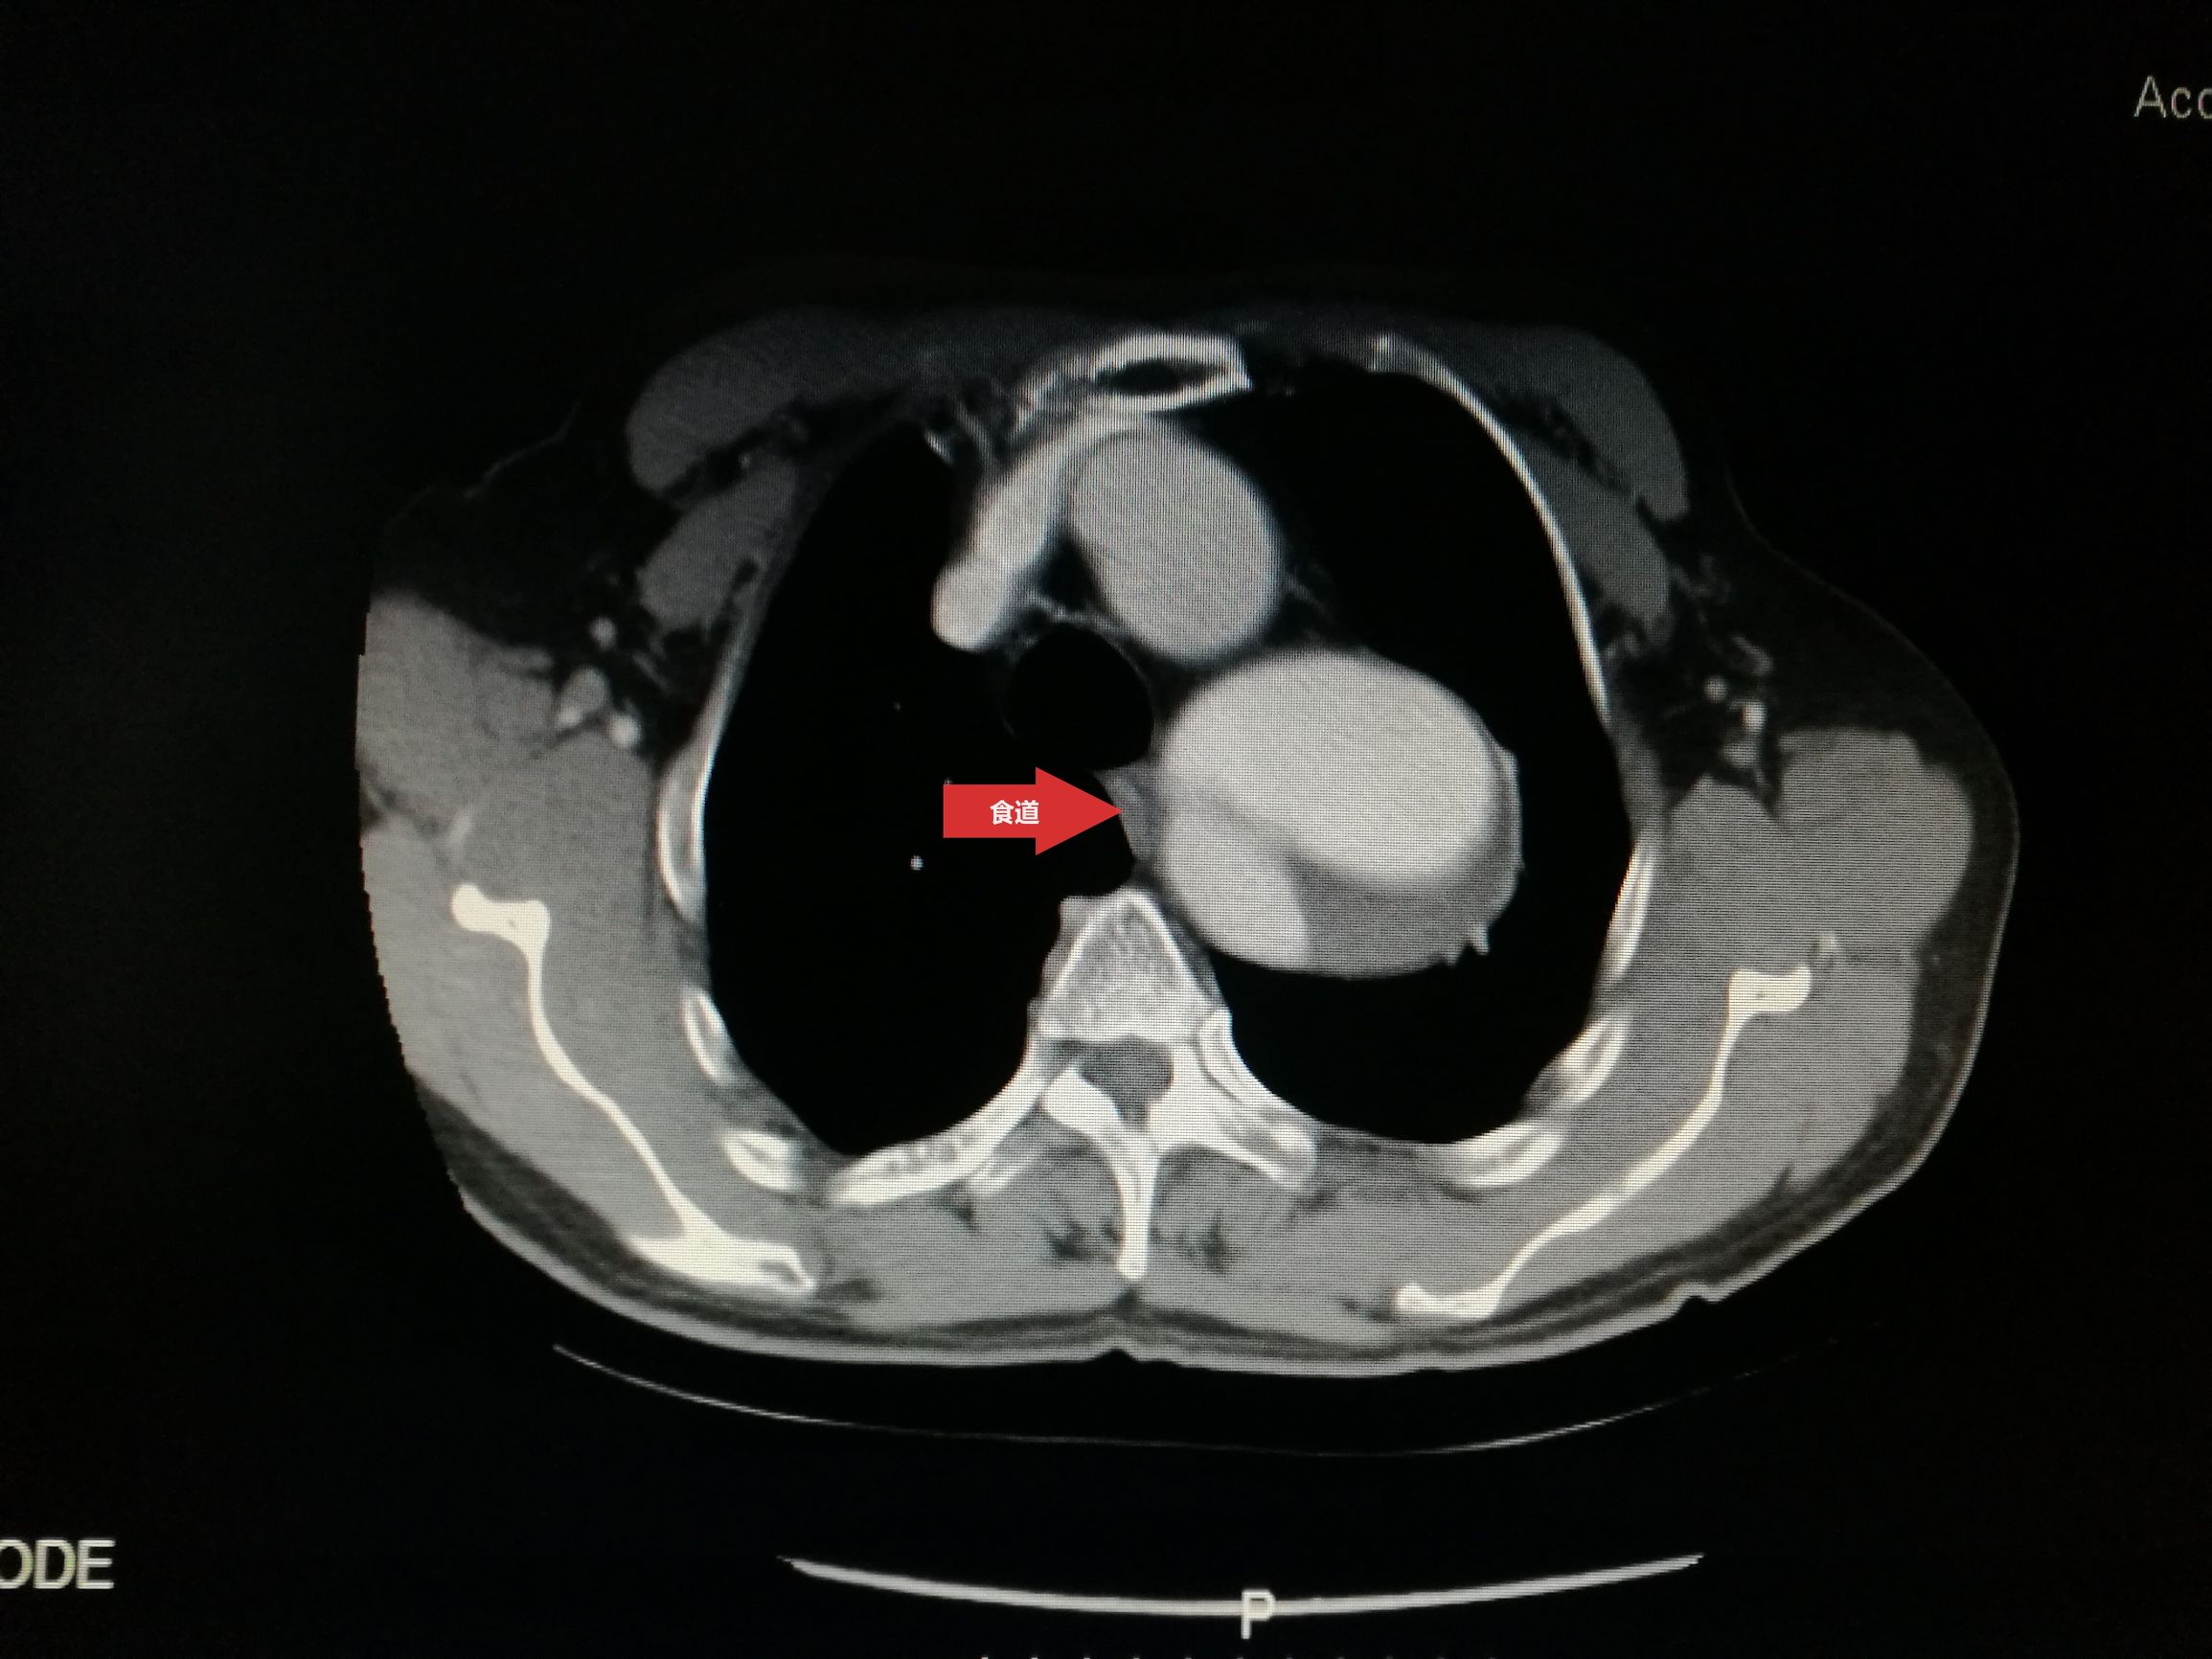

此例患者进行发病时未能确诊,进入慢性期后假腔扩张瘤样变。在CT的部分层面,食道受压看不到。重建影像可见假腔扩张,动脉扭曲。